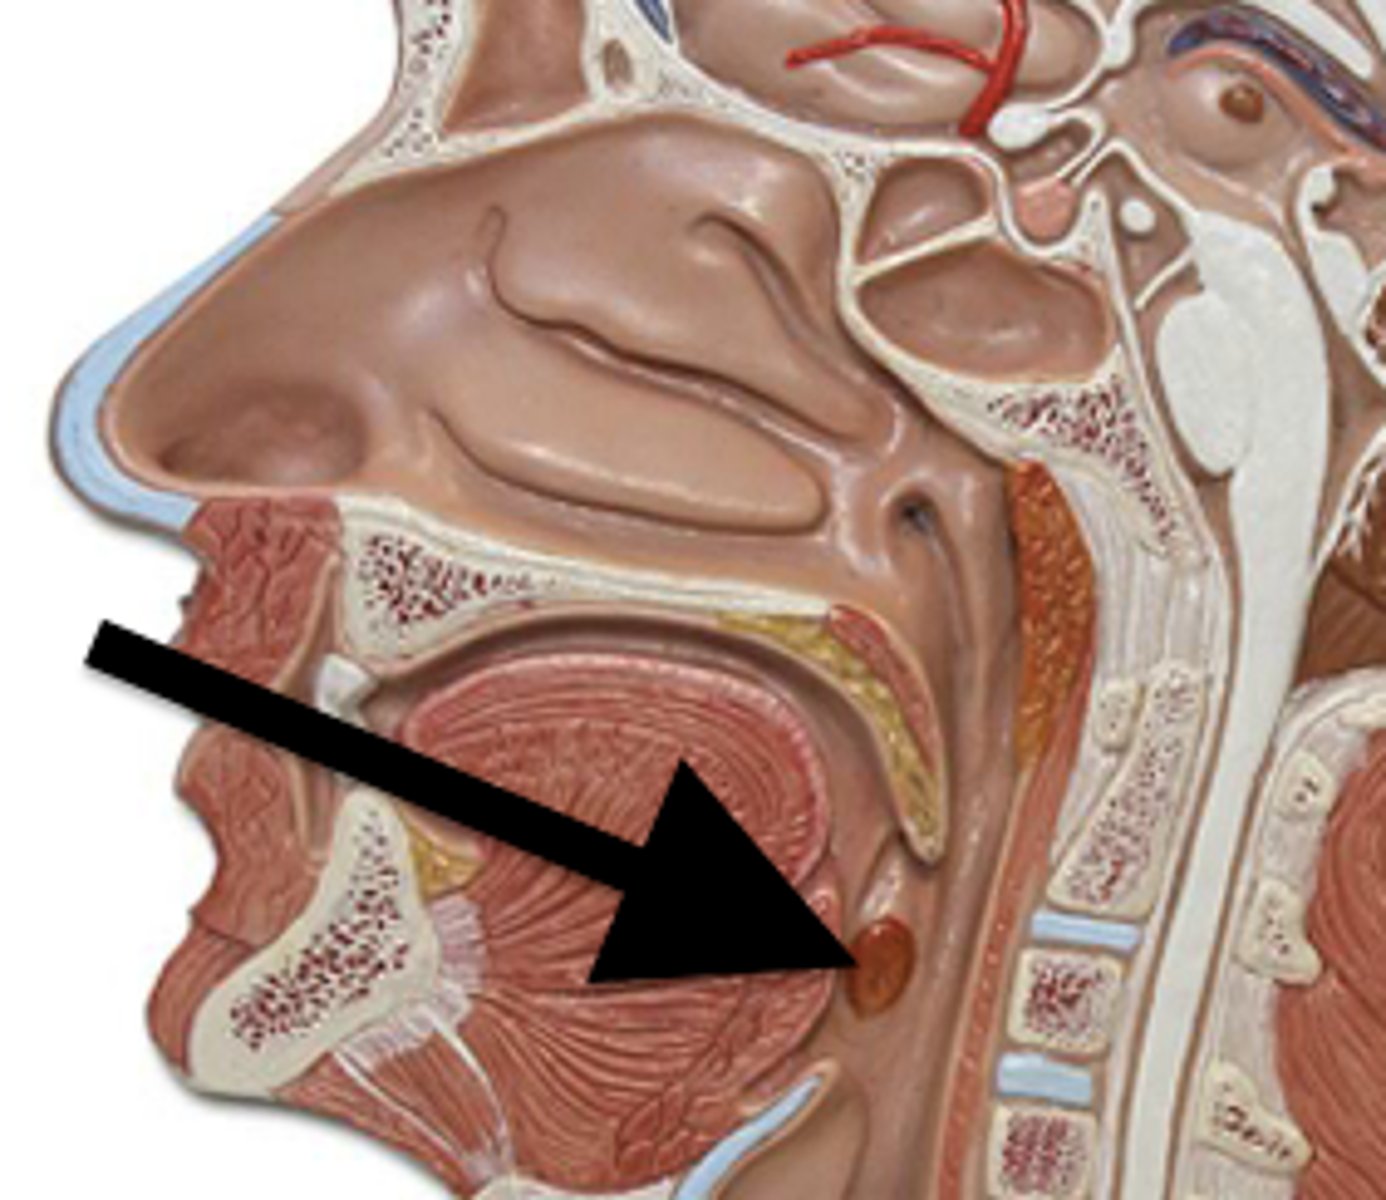

tonsils

form a ring of lymphatic tissue around the openings to the pharynx.

palatine tonsils

are found on the lateral walls of the oral portion of the pharynx (the oropharynx). These tonsils are in prime position to "catch" pathogens being ingested with food.

lingual tonsils

reside on the superior surface of the posterior tongue. These tonsils are in prime position to "catch" pathogens being infested with food.

tonsillar crypts

contains lymphocytes and bacteria. Deep to the epithelium and adjacent to the crypts you can see dense lymphatic tissue

tonsillar capsule

made of dense connective tissue. It separates the tonsil from the subjacent tissues. Helps prevent the spread of infection.